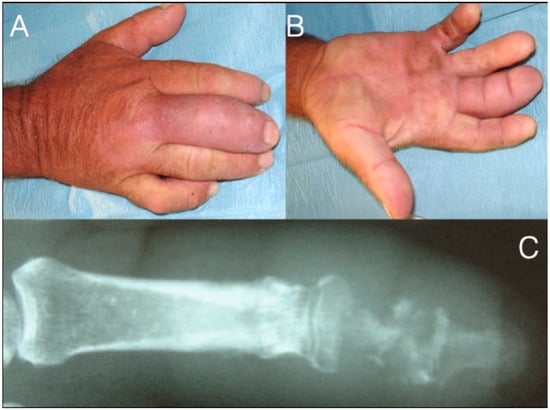

Figure 6. 71-year-old farmer with a fusiform middle finger after penetrating injury 17 days ago through the dorsal skin just proximal to the DIP joint (A,B). He received analgesics and ampicillin per os in the last six days. The patient developed osteomyelitis of the middle phalanx and septic arthritis of the DIP joint (C). After debridement he underwent amputation at the PIP joint level.